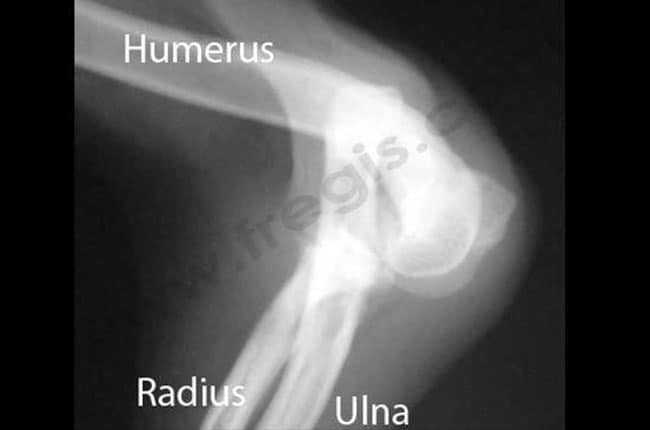

Un examen radiologique permet de confirmer le diagnostic, de préciser le type de luxation, d’évaluer d’éventuelles anomalies articulaires pouvant prédisposer à la luxation, et de faire un bilan des éventuels remaniements articulaires (arthrose, remodelage des condyles huméraux, de la fosse olécranienne, de l’incisure trochléaire) [2].